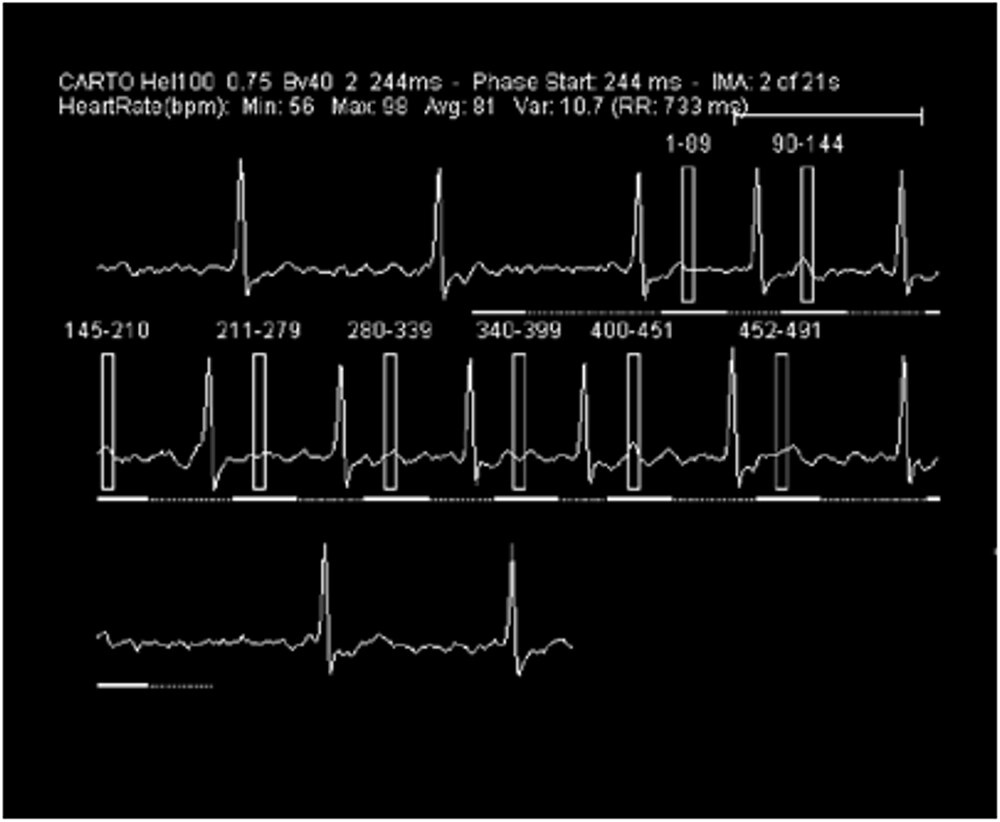

図6.撮影時心電図波形

心拍数 56-98 bpm、不整脈あり、β遮断薬使用せず。